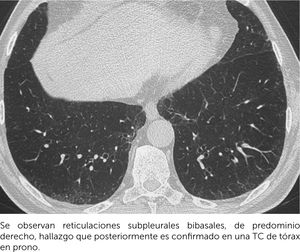

Rol de la radiología torácicaLa herramienta imagenológica más útil en el diagnóstico de estas patologías es la TCAR, que proporciona información anatómica detallada del parénquima pulmonar. Es crucial realizar el examen con cortes finos (menos de 1,5mm) y utilizando algoritmos de reconstrucción de alta frecuencia espacial, en inspiración y evitando artefactos de movimiento. Las reconstrucciones multiplanares (coronal o sagital) pueden ser útiles, especialmente en la evaluación de la distribución cráneo-caudal y en diferenciar áreas de panalización versus bronquiectasias periféricas. Adicionalmente, se pueden adquirir imágenes en espiración cuando se desea evaluar enfermedad de la vía aérea pequeña, detectando atrapamiento aéreo (sospechoso de HP fibrótica). Las imágenes adicionales en decúbito prono son útiles en estos pacientes pues permiten diferenciar el compromiso intersticial subpleural inicial de las atelectasias por decúbito y muchas veces ayudan a distinguir algunos hallazgos subpleurales característicos de ciertos patrones de EPID (respeto subpleural y áreas de panalización)8,9.

Se considera anormalidades intersticiales pulmonares (ILAs, por sus siglas en inglés) a los hallazgos pulmonares que incidentalmente se detectan en un tomografía computarizada (TC) parcial (de abdomen, por ejemplo) o completo de tórax, que pueden representar potencialmente una EPID sin existir la sospecha diagnóstica de esta enfermedad. Estos hallazgos pueden ser opacidades en vidrio esmerilado, reticulaciones, bronquiectasias/bronquiolectasias por tracción y/o quistes no enfisematosos; que deben comprometer las regiones no dependientes (superiores o ventrales) y más del 5% de cualquier zona pulmonar. Estas alteraciones se subcategorizan según la distribución y la presencia de fibrosis en ILA no subpleural, subpleural no fibrótica, y subpleural fibrótica; siendo aquellas subpleurales fibróticas las que más tienden a la progresión. La diferenciación entre ILAs y EPID clínica y subclínica se basa en los antecedentes clínicos. La ILA no implica ausencia de síntomas respiratorios o deterioro funcional, y en el caso de existir estos puede representar una enfermedad pulmonar intersticial leve. Se ha demostrado que la ILAs son más prevalentes en pacientes de mayor edad y en aquellos con hábito tabáquico. La importancia clínica de este diagnóstico imagenológico es que estos pacientes además de poder evolucionar a una enfermedad pulmonar intersticial, tienen un riesgo significativamente mayor de muerte por cualquier causa12. (Figura 7).